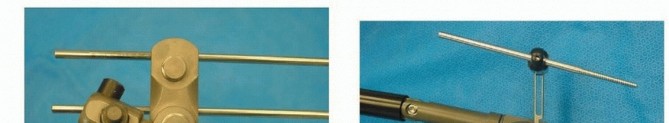

]). B. An obturator outlet view identifies the proper pin entry site. C,D. An iliac oblique view with cephalad angulation directs the advancing pin. E,F. The rollover view (obturator oblique inlet view) ensures pin placement within the inner and outer tables of the pelvis. Intercortical pin orientation within the tables of the pelvis is monitored on an obturator oblique inlet view (“rollover view”) ( TECH FIG 4E,F). A 5-mm diameter, 50-mm thread length pin is inserted to the depth of the threads. A second pin may be inserted proximal to the first, if desired. 3. ## Frame Application and Reduction No frame, regardless of complexity, restores sufficient definitive fixation to vertically unstable lesions. 22 Accordingly, simple constructs are preferred to permit patient mobilization, abdominal access, and performance of subsequent diagnostic and therapeutic procedures. Accurate pin placement within the curved iliac crest mandates a nonparallel converging pin pattern. Pin clamps with a straight configuration require that pins be prestressed to conform and accommodate such clamps ( TECH FIG 5A). Those with an independent ball joint design offer an attractive alternative (TECH FIG 5B). 319

---

TECH FIG 5 • A,B. Pin clamps: straight and multiplanar. Applied pin clamps should remain three fingerbreadths above the skin surface. This is less threatening to subjacent soft tissues and permits adequate pin tract care. The frame is fabricated with inclusion of universal ball joints and reduction is performed. AP compression injuries are reduced with midline-directed compression and lateral compression injuries with distraction. Adjunctive lower extremity skeletal traction may be considered for vertically displaced patterns. Bar-to-bar connectors are next secured and operative incisions are closed and dressed. 4. ## Pelvic Antishock Clamp: C-Clamp The surgeon can choose between two coronally oriented pin placement positions (anterior or posterior) ( TECH FIG 6A).20 Anterior pins are placed in the dense column of bone of the gluteal ridge. Anterior pin placement will allow for compression of the anterior and, to some degree, the posterior pelvic ring. Posterior pin placement allows for compression of the posterior pelvic ring.